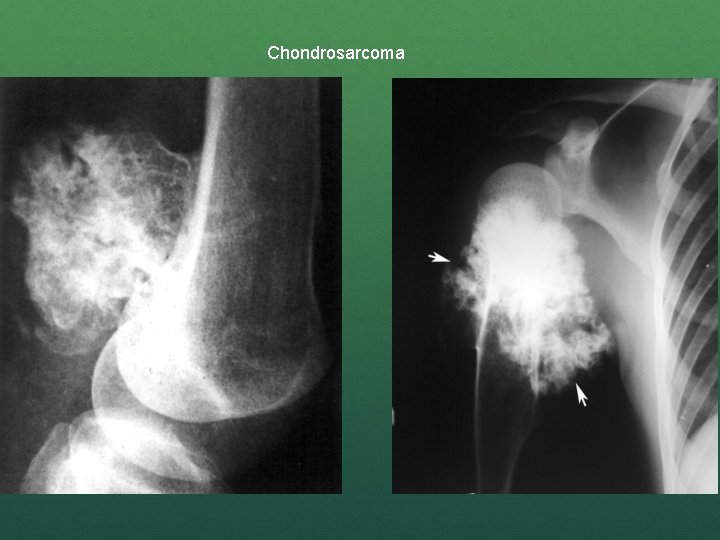

Investigations X – ray – Chondrosarcoma is a fusiform, lucent defect with scalloping of the inner cortex and periosteal reaction. Extension into the soft tissue may be present as well as punctate or stippled calcification of the cartilage matrix.

Chondrosarcoma